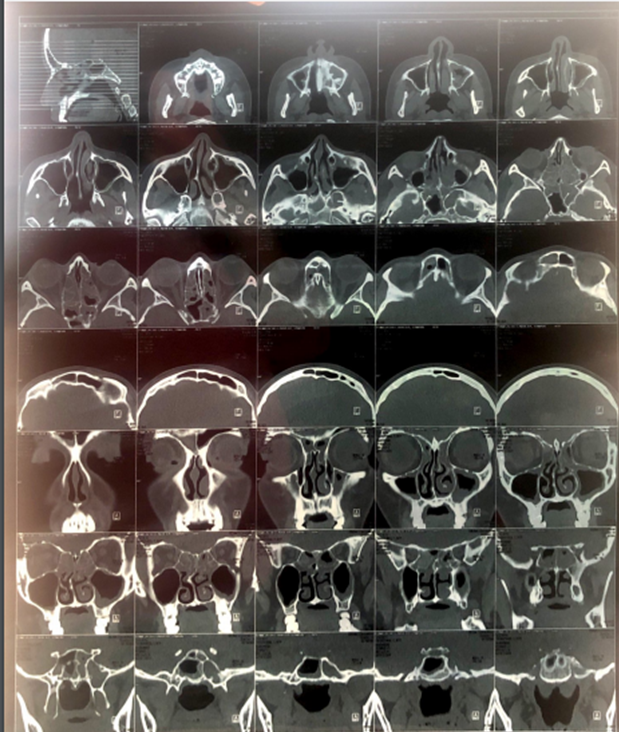

El diagnóstico clínico es de sinusitis, y se prescribe tratamiento con 1 gr de amoxicilina + ácido clavulánico. Se solicita TAC en la que se reporta ocupación mucoperióstica de los senos frontal, esfenoidal y antros maxilares, con ocupación casi completa de las celdillas etmoidales. Además del septum nasal desviado a la derecha, con espolón óseo y cornetes nasales engrosados (Fig. 1)

.Figura 1. Tomografía Axial Computarizada de Senos Paranasales

Importante ocupación mucoperiostica, de los senos frontal, esfenoidal y antros maxilares, con ocupación casi completa de las celdillas etmoidales. Septum nasal desviado a la derecha, presenta espolón óseo, cornetes engrosados